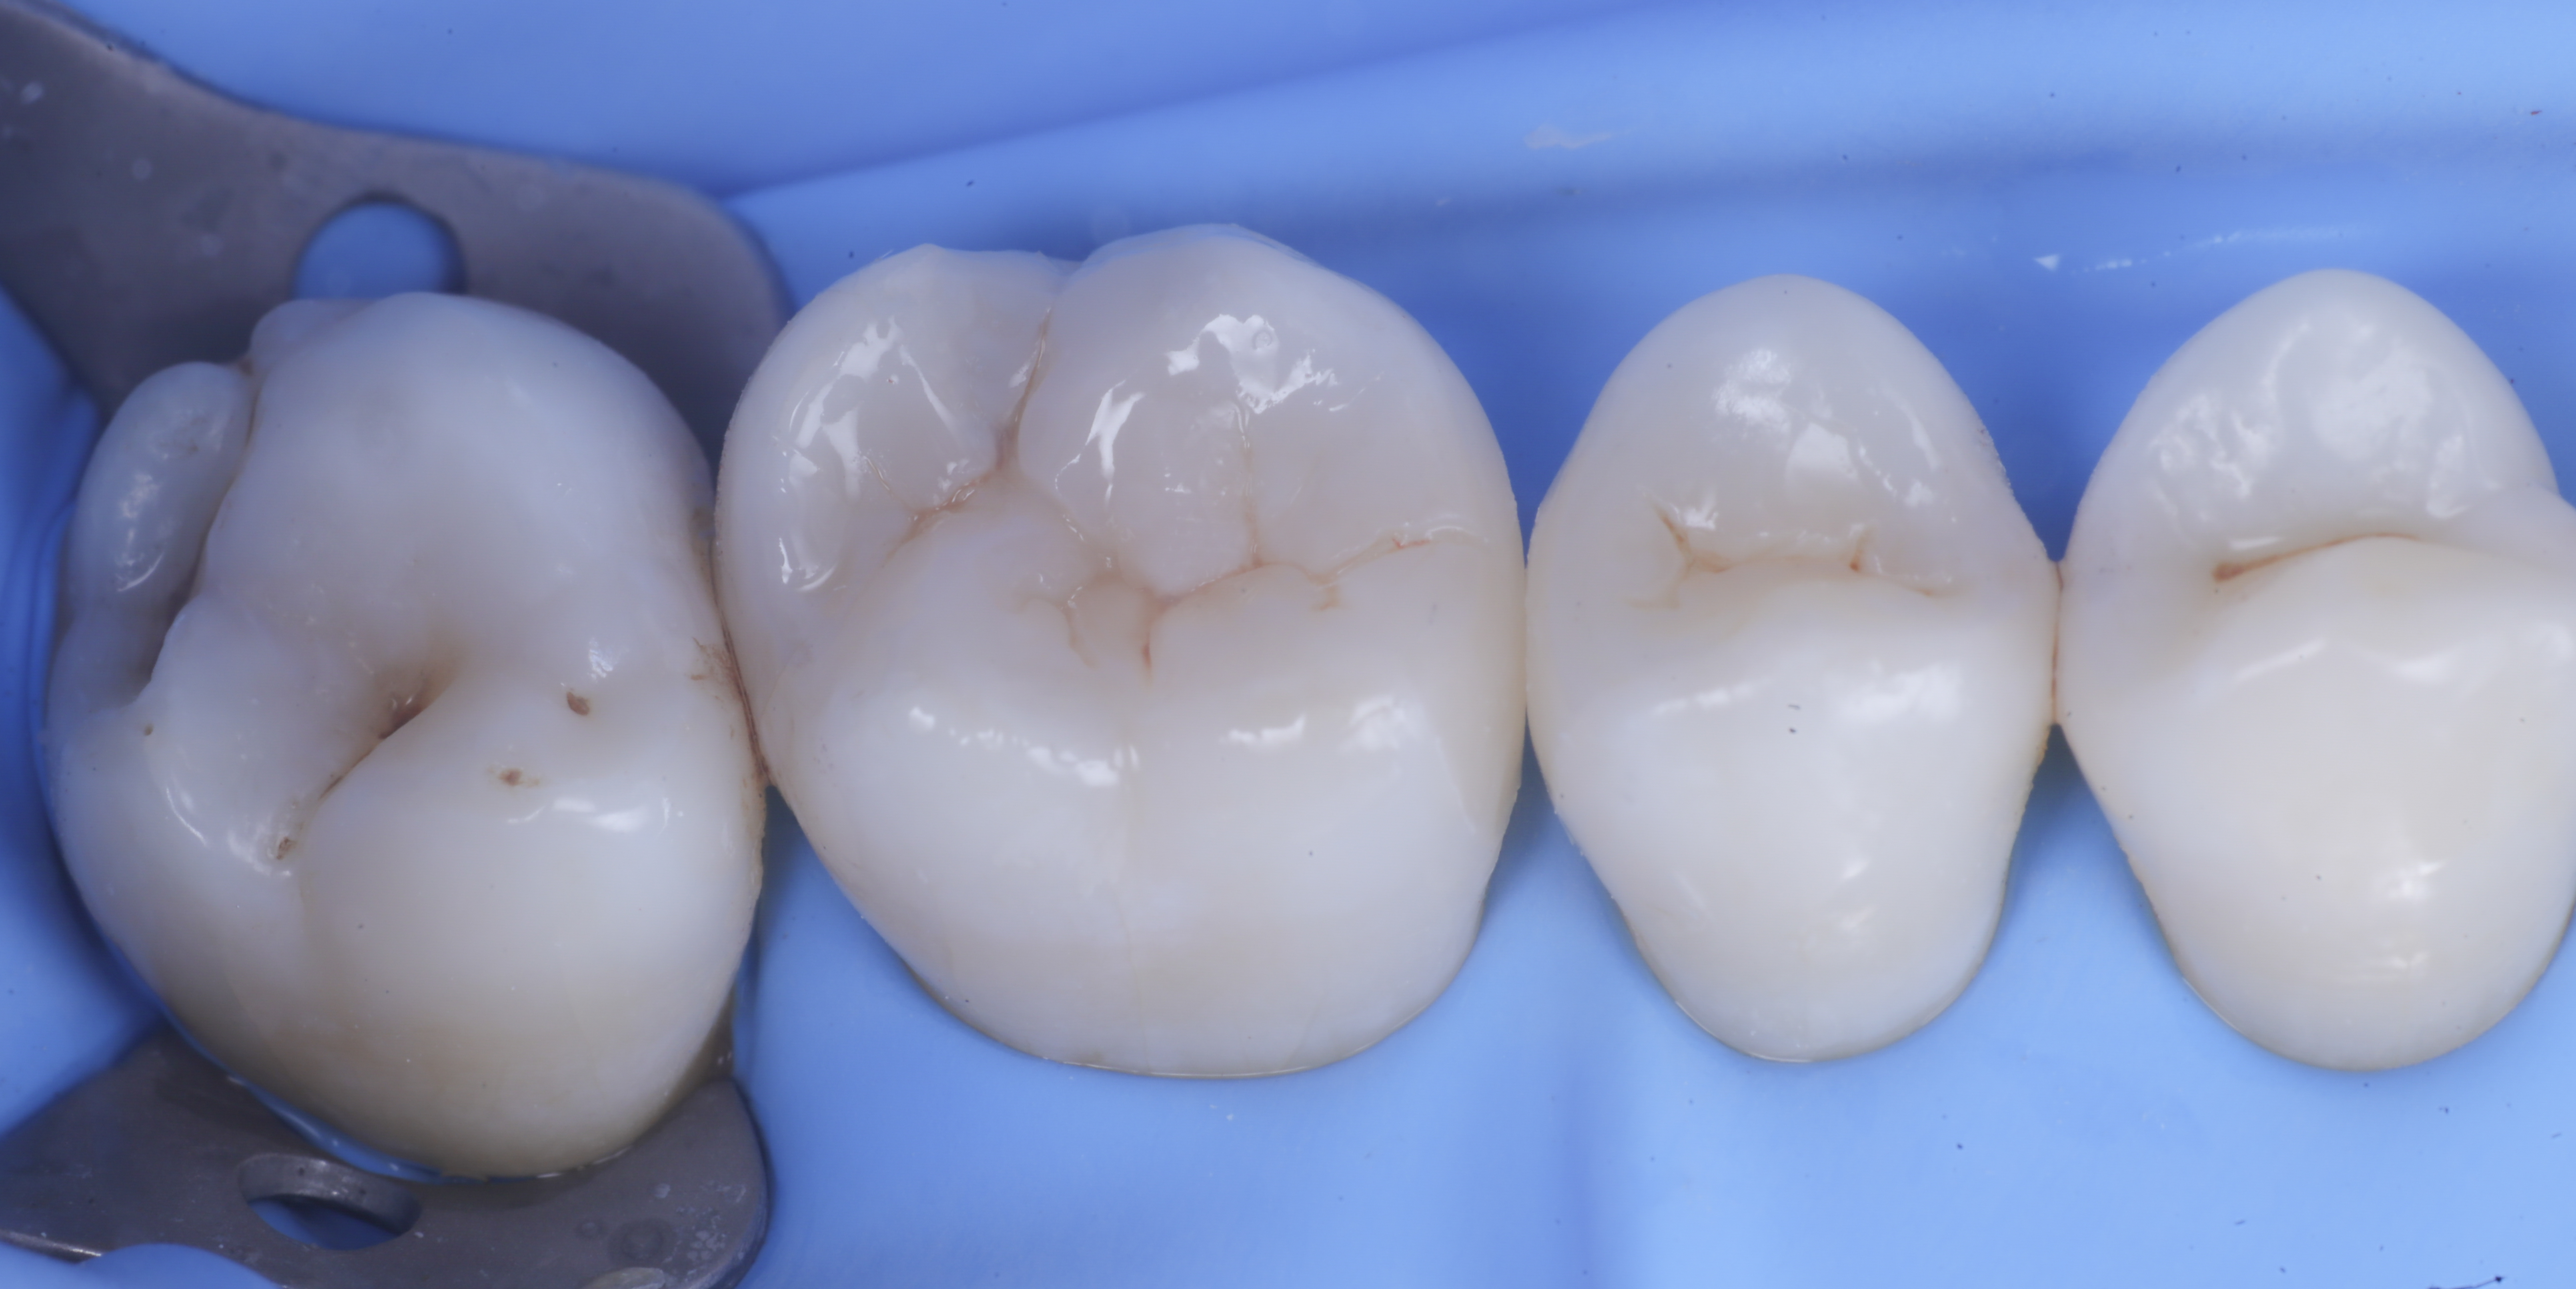

foto 1 Fotografia iniziale